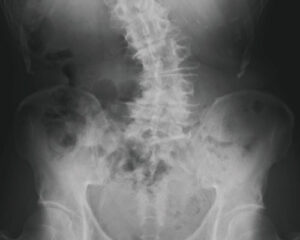

椎間板の変性段階(D1~D6)

D4 5~10年経過

椎間板の変性が慢性化したステージで、サブラクセーションが5~10年放置されている状態になります。椎間板の水分は放出され、椎間板スペースの元の厚さの2/3まで減少し骨の変形が始まります。上下の椎骨が接近し可動性が制限され、神経への負荷を避けるための防御反応により、カルシウムが沈着し補強を始めます。ケアをしても椎間板スペースや骨の変形には変化が見られませんが、神経機能が改善することは可能です。